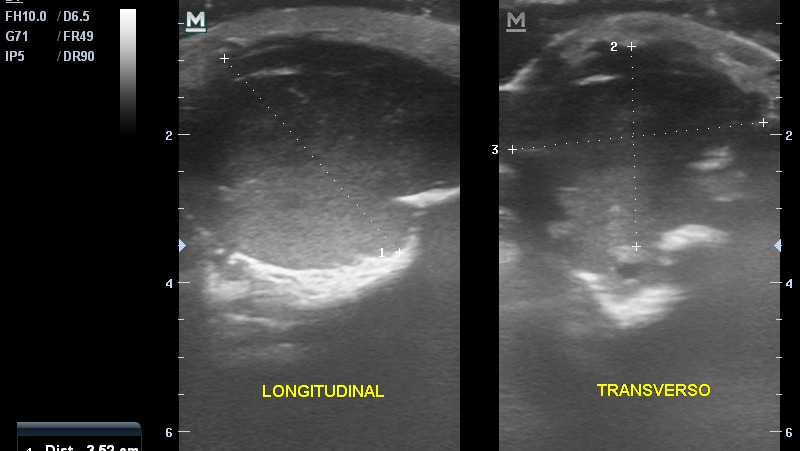

Hola, me llamo Gael. Estoy recaudando fondos y requiero de tu ayuda porque necesito operarme nuevamente del brazo. Ya fui sometido a una intervención quirúrgica en la que se removió una lesión tumoral que me salió en la muñeca derecha. Gracias a una biopsia que requirió una intervención quirúrgica ambulatoria, descubrimos que se trataba de un tumor de CÉLULAS GIGANTES. Aunque se supone que tiene carácter benigno, fue muy agresivo: empeoró muy rápidamente después de la primera biopsia (me hicieron una segunda en Caracas para confirmar), provocó gran pérdida ósea y tenía potencial de malignidad si no se atacaba inmediatamente. El tumor que se removió pesó aproximadamente 2 kilos. Gracias a Dios, la tercera biopsia de la pieza confirmó nuevamente el diagnóstico, lo que permite que me hagan cirugía reconstructiva y no una amputación, que estuvo entre las opciones médicas propuestas. Sabemos desde ya que perderé la movilidad de la muñeca. Los doctores aún están decidiendo el plan quirúrgico: están entre hacerme un raspado óseo del peroné para insertarlo en el radio (hueso del brazo que se vio afectado) para que se solidifique, o colocarme el cúbito de manera central, para que sea el único hueso de mi antebrazo. Parece que tienden hacia la segunda opción, dado que la pérdida ósea es de al menos 10 centímetros. La primera se trató de una operación de gran envergadura, que duró más de ocho horas y requirió de un gran equipo especializado: cirujano, especialista en cirugía de mano y especialista en tumores óseos, además de varios doctores asistentes. Logramos manejarlo a través de la salud pública, en el Hospital Pérez Carreño, en Caracas. La salud en mi país, Venezuela, lamentablemente está en situación de crisis y a pesar de contar con profesionales de gran talla, todos los insumos quirúrgicos y medicamentos deben ser cubiertos por mi familia. Eso sin contar el hecho de que hemos tenido que permanecer más de un mes fuera de nuestro hogar en una ciudad ajena y haciendo diligencias que requieren muchos gastos de movilización. He contado hasta ahora con mucha solidaridad de amigos, vecinos, familiares e instituciones, pero aún necesito un poco más de apoyo para concluir esta etapa amarga de mi vida y recobrar mi salud, dentro de las posibilidades. Soy diestro, así que esta lesión ha complicado mi calidad de vida y mis posibilidades de movilidad, al igual que mis actividades como atleta. Sin embargo, estamos esperanzados porque al menos no se trató de un carcinoma (lo que se temió antes de las biopsias) y no necesitaré tratamientos químicos, tan solo otra intervención quirúrgica, que si bien es de gran envergadura, será realizada por un excelente equipo médico en el que confío plenamente para ayudarme a recuperar mi salud. Si está dentro de tus posibilidades ayudarme con una donación, te estaré agradecido eternamente; cualquier cifra es bienvenida por pequeña que sea: todo suma. También te agradezco la difusión de esta información por todas las plataformas que te sean disponibles, así como los posibles contactos con instituciones gubernamentales o benéficas que puedan ayudar. Todos los aportes serán eternamente agradecidos. De igual manera, si estás en situación de DONAR SANGRE en la ciudad de Caracas, ese aporte también será bienvenido. Dios te bendiga y reponga tu ayuda en salud y bienestar. Si quieres donar en *bolívares*, puedes hacerlo a la cuenta de mi mamá: Alejandra González Poleo Provincial Corriente 0108 0977 1701 0020 5079 Para pago móvil: Ci 14491428 Telf 04125384544 Si quieres donar en *Euros* puedes hacerlo a la cuenta de mi papá: Fernando Enrique López González: ES7820800144853000032790 (Abanca) Si quieres donar en *Zelle* o donar *sangre* comunícate con mi mamá al +584125384544 y ella coordinará para hacer efectivo tu aporte. También puedes donar en el sitio GoFundMe. Mil gracias!!! https://gofund.me/3bf10d25